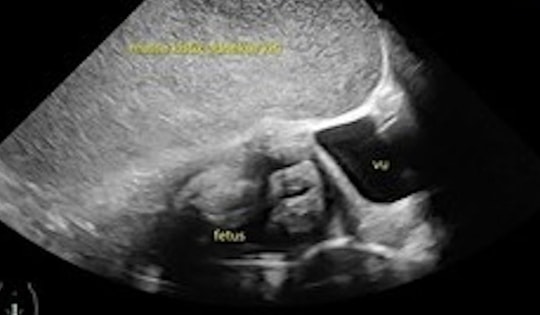

Siêu âm phát hiện thai nhi mắc bệnh tim bẩm sinh

Bác sĩ siêu âm thai nhi tuần thứ 22 phát hiện bị dị tật tim bẩm sinh nên lên kế hoạch theo dõi, điều trị ngay khi bé chào đời.